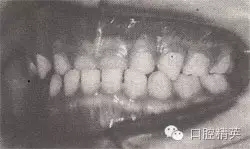

治療時(shí)間:1.5個(gè)月,乳前牙反頜解除,乳切牙達(dá)到正常覆頜、覆蓋。下頜回到正常位置。

圖8-37 安氏Ⅲ類錯(cuò)頜,乳前牙反頜矯治前后面頜像

矯治后咬合圖